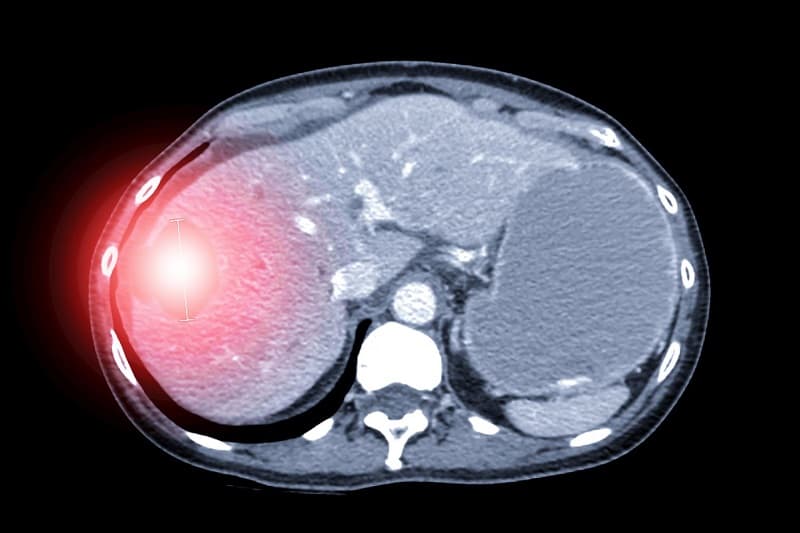

2. Mức độ u gan vỡ trong chấn thương bụng kín

Hiệp hội Phẫu thuật Chấn thương Hoa Kỳ đã chia mức độ u gan bị vỡ thành 6 cấp độ từ nhẹ đến rất nặng, giúp bác sĩ đánh giá tổn thương và quyết định hướng điều trị.

Tụ máu chiếm > 50% gan hoặc trong nhu mô có khối tụ máu >10 cm. Nguy cơ chảy máu cao, có thể cần can thiệp.

2.4. Vỡ gan độ 4

Tổn thương nhu mô gan rộng gây vỡ từ 25% đến 75% một thùy gan (gan được chia thành các thùy và tiểu thùy theo Couinaud). Vỡ từ 1 đến 3 tiểu thùy Couinaud trong một thùy gan.

2.5. Vỡ gan độ 5

Tổn thương nhu mô gan gây vỡ lớn hơn 75% một thùy gan, hoặc vỡ hơn 3 tiểu thùy Couinaud trong một thùy gan. Có thể ảnh hưởng các mạch máu chính của gan (như tĩnh mạch gan, động mạch gan) hoặc các mạch máu lớn lân cận gan.

2.6. Vỡ gan độ 6

Mức độ tổn thương nghiêm trọng nhất, thường rất hiếm gặp nhưng cực kỳ nguy hiểm. Gan bị dập nát hoàn toàn, không còn hình dạng, cấu trúc giải phẫu bình thường. Có nguy cơ tử vong cao.